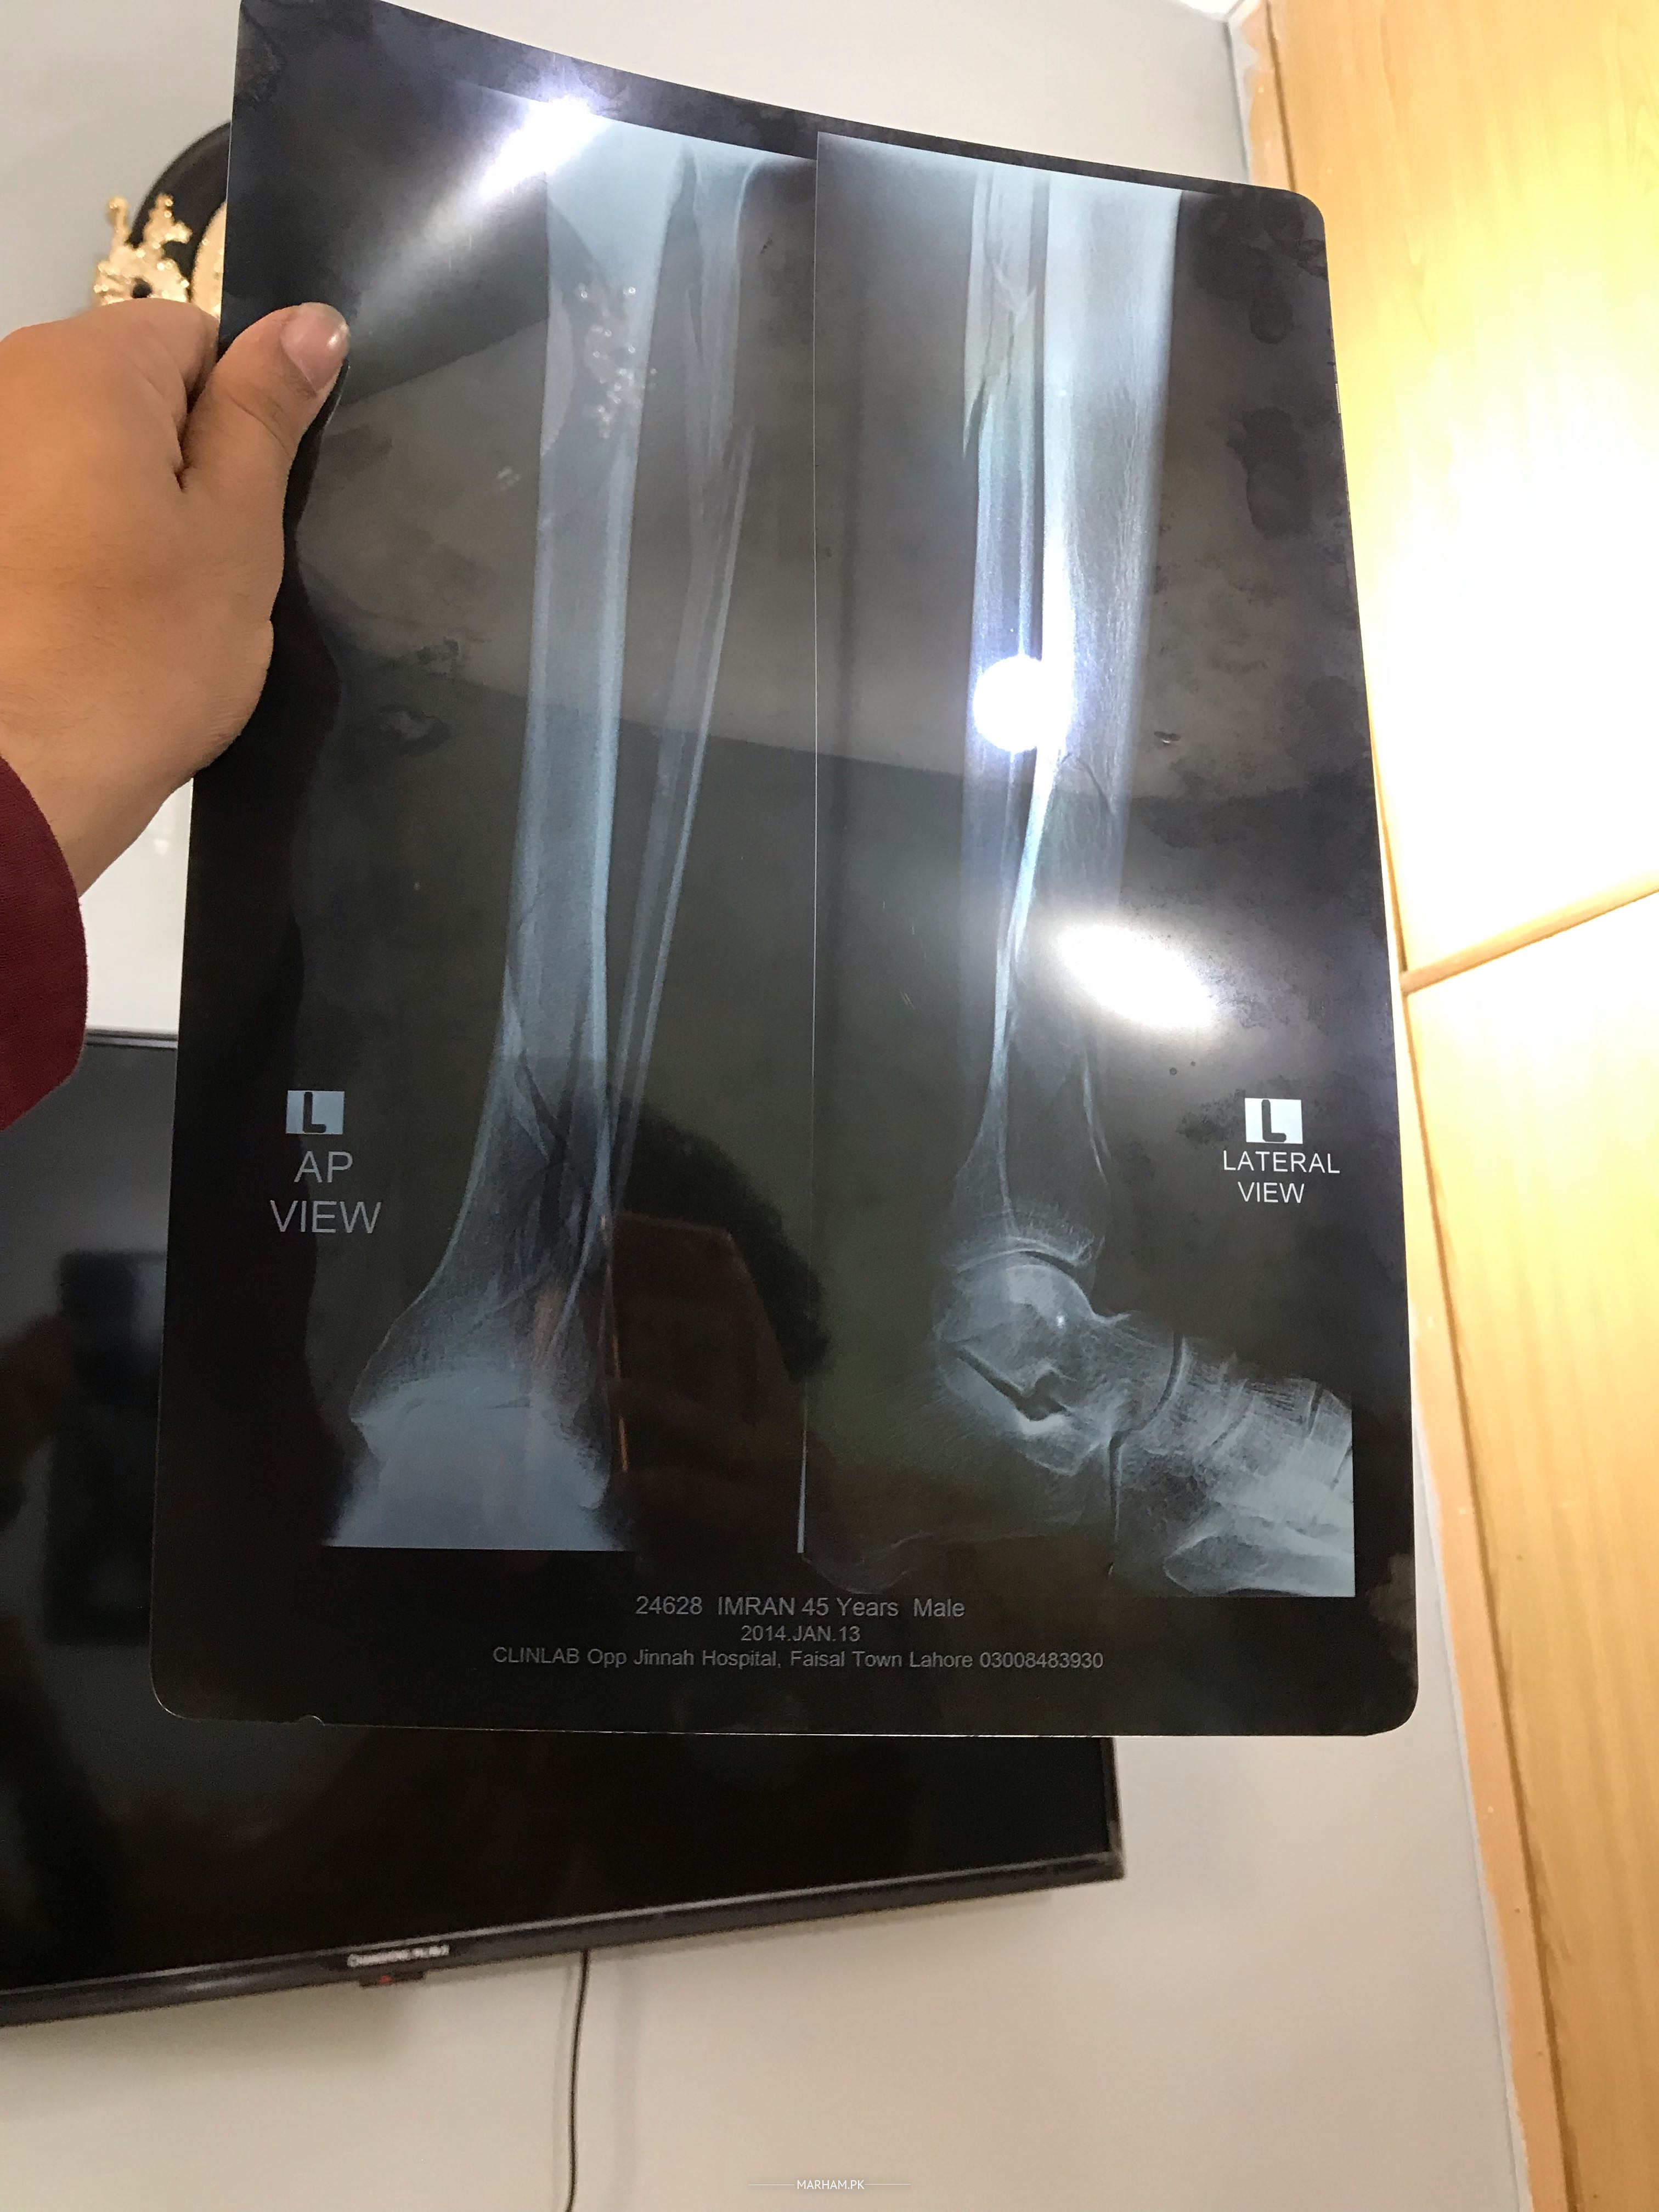

Assalamoalikum Father ki leg ma se plate nikalwai thi maximum 5 months pehle unki pain abhi taq nai gai unko plate nikalne k bad still pain ha pahle b pain thi jiski wjha se plate nikalwai thi plate nikalwane se pain kam hoi ha phle se laqin abhi b still pain ha or father ki health week ho gai ha Kuch suggest kr den Kindly koi medican ya kuch suggest kr den wo Dr k pass jane se bhut ghabraty Allah apko khush rakhy Shukrea Allah hafiz before and after pics and xray b opration se pehle ki or opration k bad ki plates lagne k bad ki b xray lgay ab plates nikal gai ha laqin pain nai ja ray xray clear ha plates nikalne k bad ka xray ki picture available nai wo dr kehty clear ha opration k bad drd chali jani chai laqin abhi taq drd nai gai

Aur fracture kaise hoa ta??? Accident hoa ta ya girh gaey teh??? Unko B. P, sugar ya koi aur bemari tu nahin.. Agar apke pass X-ray hain tu kindly share karen??

Apke father ke X-ray main ne dekain hai. Ye complex fracture ta. 2 bones ka fracture multiple jaga tah.. Unko numbness ya leg sun tu nahin hojate??